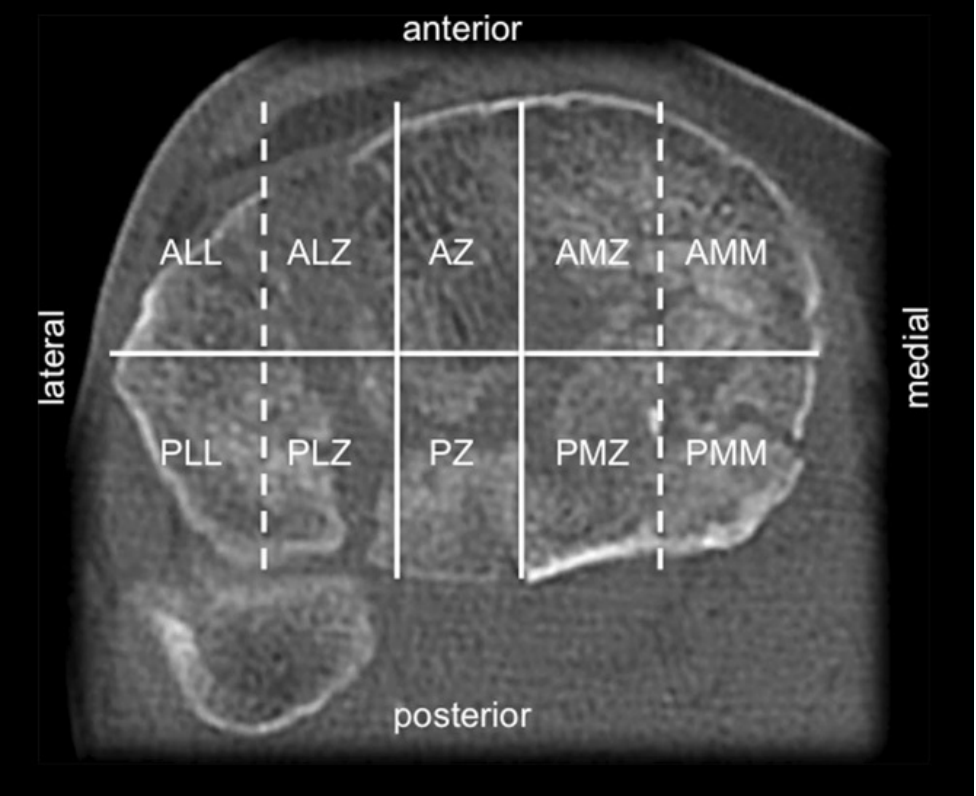

十段分型(Krause et al., 2016)

2016年Krause等学者发表了基于CT检查的三维分型系统。该分型将胫骨平台细分为10个解剖节段(图1),实现了对骨折定位的精确解析与系统描述。根据受累节段的分布特征,可明确最佳手术入路选择,既能实现骨折的精准复位固定,又能充分显露关节面。

图1:Krause等学者提出的10段分型系统具体分区如下:ALL/前外侧外侧区、ALZ/前外侧中央区、AMM/前内侧内侧区、AMZ/前内侧中央区、AZ/前中央区、PLL/后外侧外侧区、PLZ/后外侧中央区、PMM/后内侧内侧区、PMZ/后内侧中央区、PZ/后中央区。